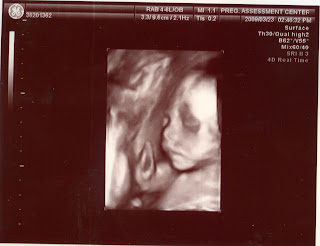

這次醫生還用4D看了傅小妹的五官,老實說,4D看起來真的很ET,連傅小弟這次看到妹妹的照片都不感興趣。

打哈欠的傅小妹 |

以前的傅小弟在肚子裡的時候,我們都沒有看過他的臉,這次還有看到傅小妹的臉,算是一種新體驗。